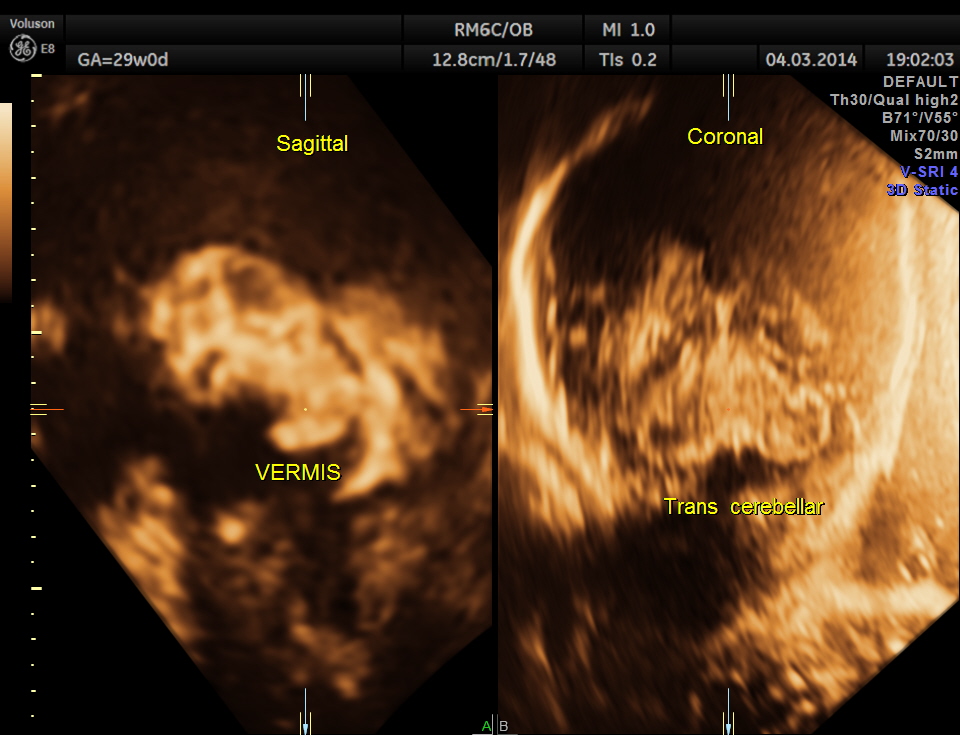

The following images were obtained. Unilateral choroid plexus cyst was seen .

Images of the other organs are given below.